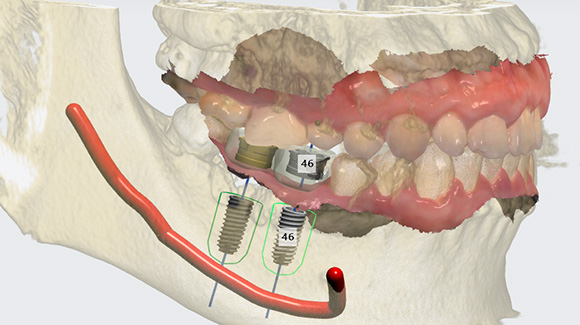

네비게이션 가이드 자체 제작

수술을 집도하시는 원장님께서 직접 임플란트 식립

위치를

디자인하셔서 훨씬 더 정확합니다.

원내에서 가이드를 자체제작하여 비용을 절감하고,

빠른

시일내로 제작이 가능하여 시간도 절감시켜드리고 있습니다.